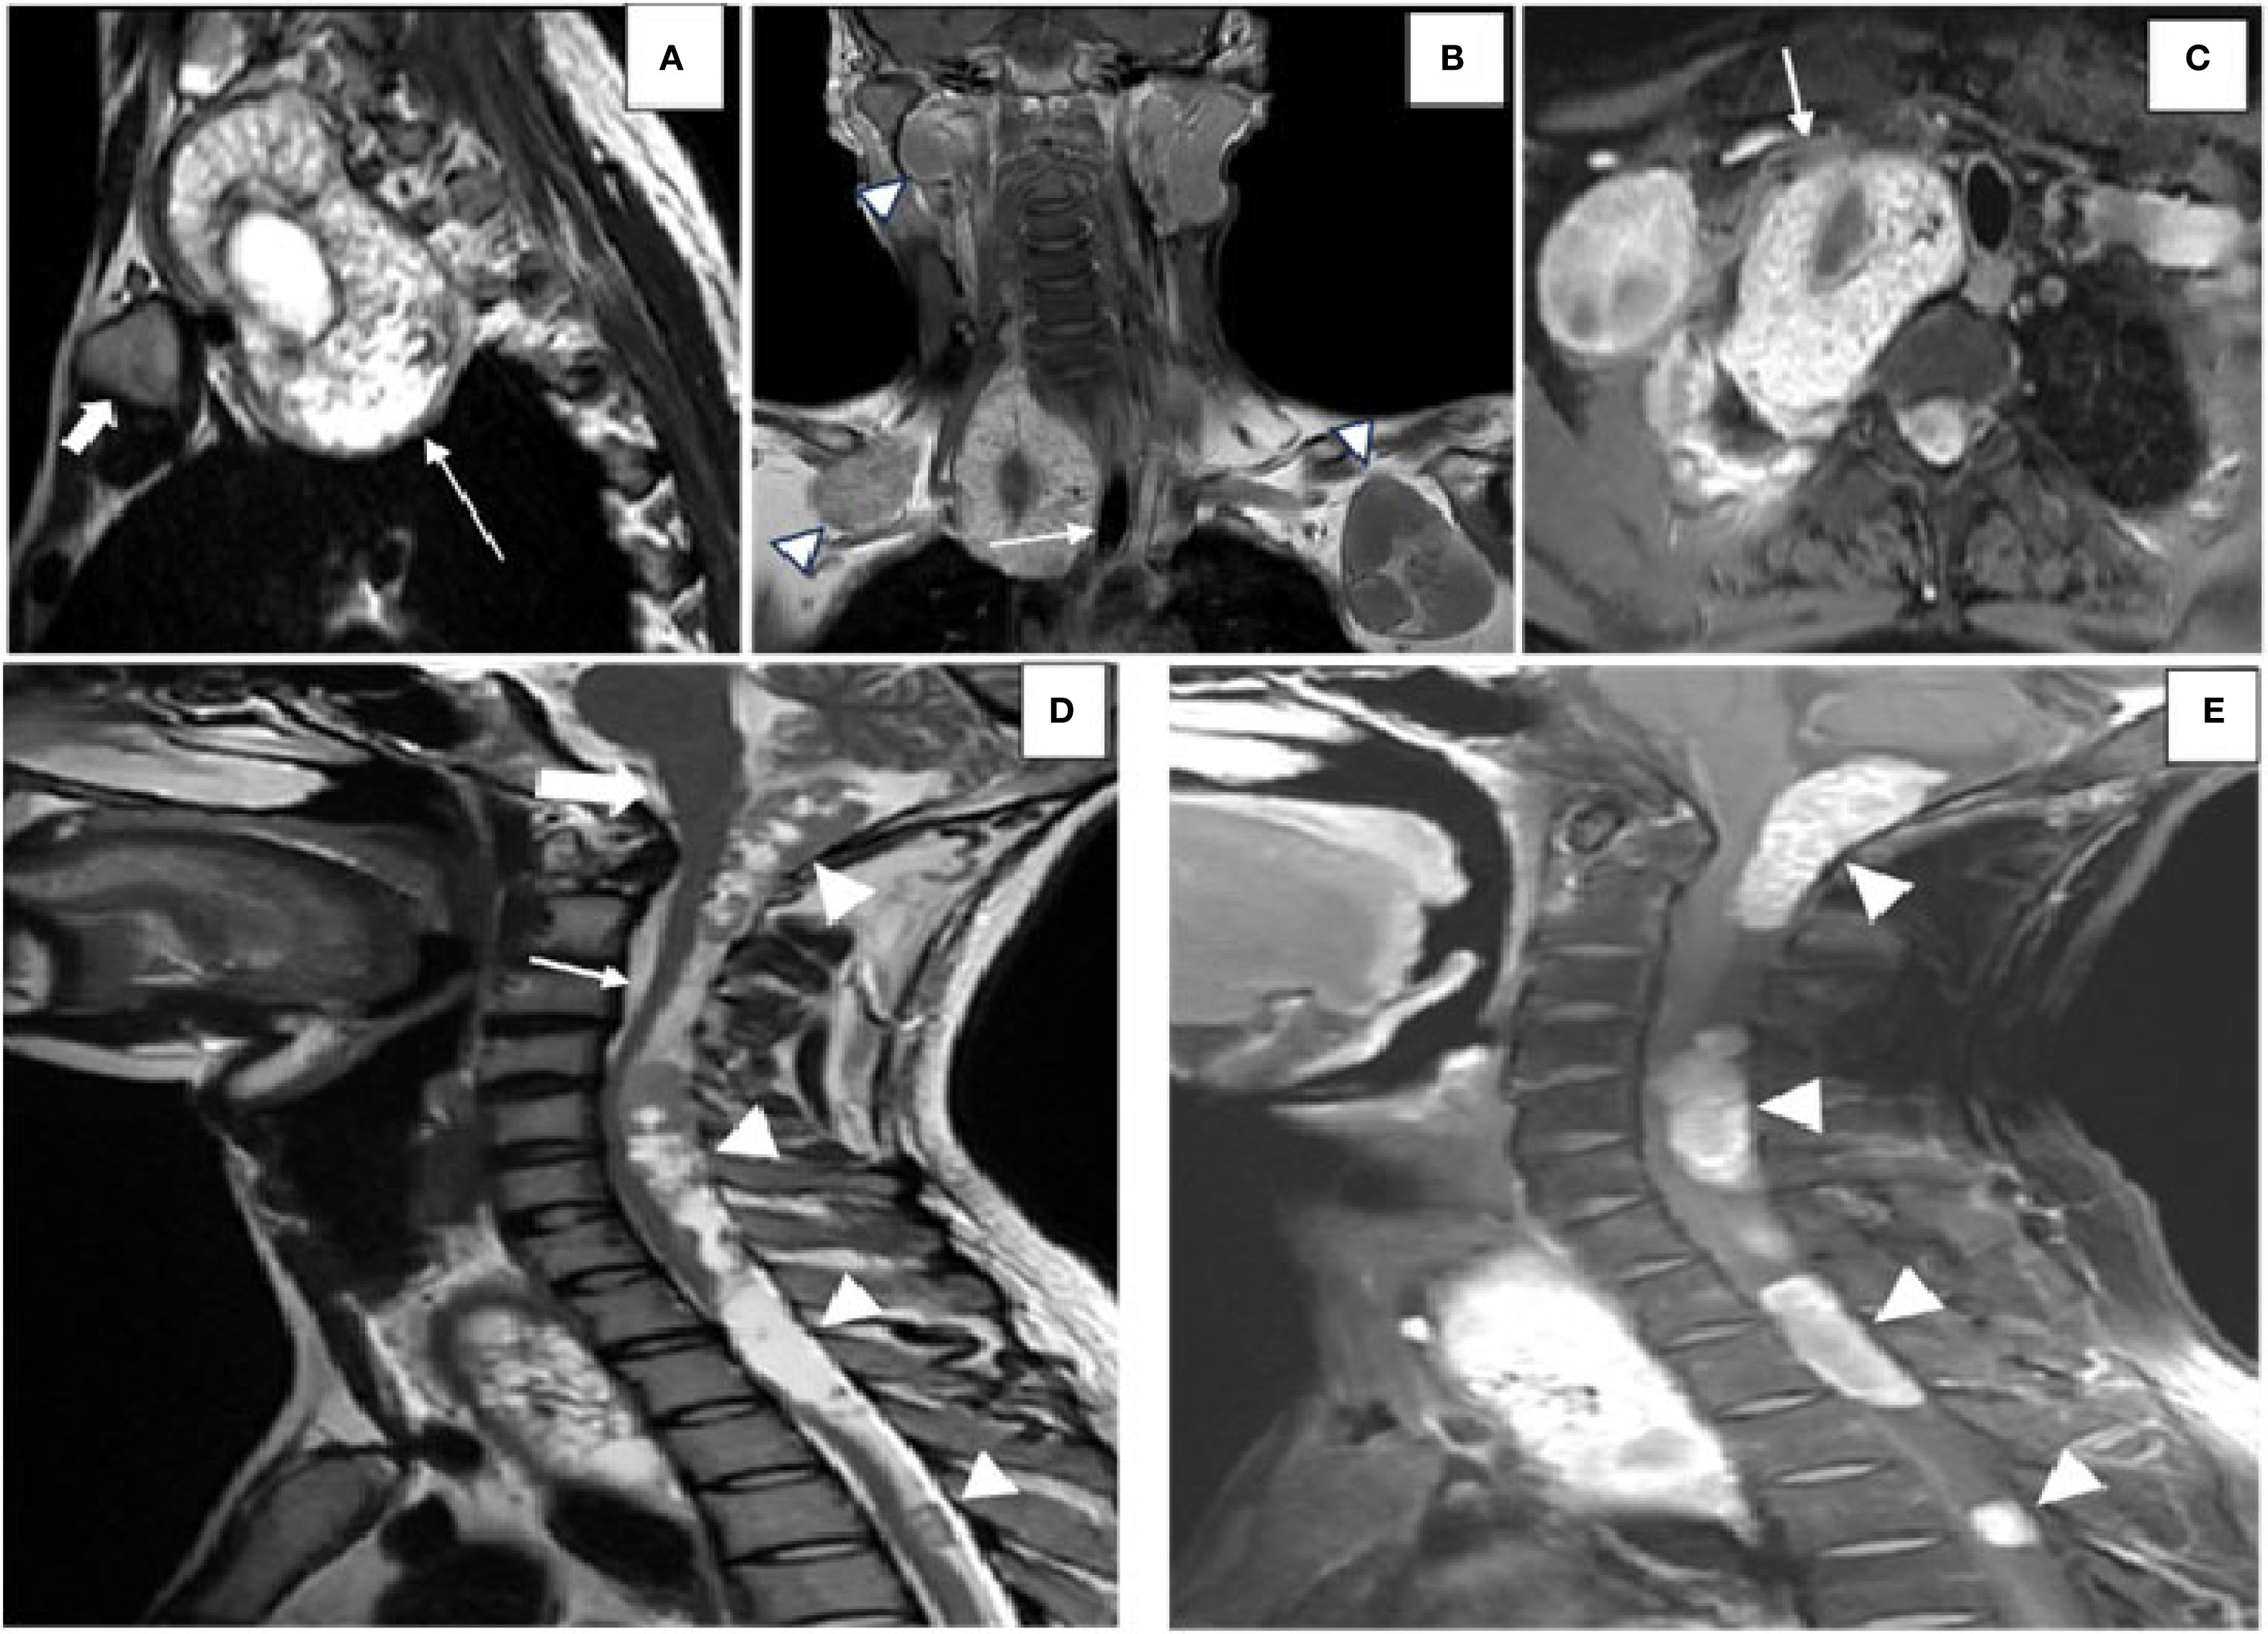

MRI with gadolinium was performed to delineate the spinal and mediastinal extension. It revealed multiple intradural extramedullary T1-hypointense and T2-hyperintense cysts with daughter cysts involving the craniovertebral junction, measuring 1.7 cm × 2.3 cm × 5 cm (AP × TD × CC), and the cervical and dorsal spine, with the largest measuring 1.3 cm × 1.2 cm × 3.7 cm (AP × TD × CC) in the upper dorsal spine, showing post-contrast enhancement (Figures 3D, E), with clear compression of the cord. A large cyst was present in the superior mediastinum, measuring 5 cm × 5 cm × 8 cm (AP × TD × CC), and was seen displacing the trachea (Figures 3A–C). Some cysts demonstrated blooming on gradient recall echo (GRE) sequences, suggesting calcification. According to the WHO-IWGE classification, the spinal and mediastinal cysts corresponded to CE1 active unilocular cysts, while the chest wall and upper limb cysts with daughter cysts and calcification were CE2 active cysts. The right thigh cyst showed peripheral calcification without daughter cysts, consistent with CE5 inactive disease.

Figure 3. Images highlighting the MRI findings of hydatid disease involving the spine, mediastinum, and craniovertebral junction. (A) Sagittal T2-weighted MRI of the dorsal spine showing a hydatid cyst (white arrow) located in the suprasternal space, predominantly on the right side, positioned posterior to the medial end of the clavicle (solid white arrow) and extending into the superior mediastinum. (B) Coronal post-contrast T1-weighted image demonstrating the hydatid cyst displacing the trachea toward the left (white arrow). Additional hydatid cysts (arrowheads) are visualized in the anterior chest wall bilaterally below the clavicles, along with an intraosseous hydatid cyst involving the right mandible. (C) Axial post-contrast T1-weighted imaging revealing the hydatid cyst indenting the subclavian artery anteriorly (white arrow). [(D) Sagittal T2-weighted MRI image displaying multiple intradural, extramedullary hydatid cysts (white arrowheads)] located at the craniovertebral junction (solid white arrow), the cervical spine (white arrow), and the dorsal spine. These cysts are seen posterior to the brainstem and the spinal cord, exerting a mass effect by displacing the cerebellar vermis superiorly and compressing the spinal cord anteriorly. (E) Sagittal post-contrast T1-weighted image showing peripheral and septal enhancement of the hydatid cysts (white arrowheads), consistent with active disease.